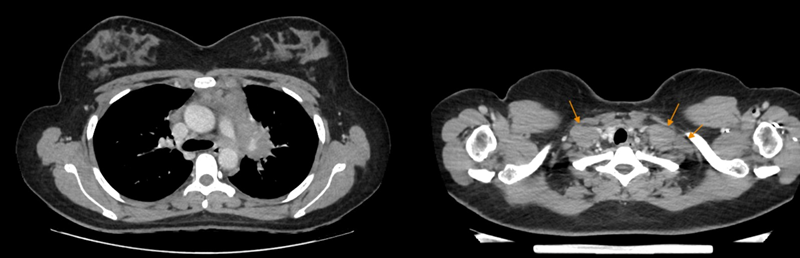

Siêu âm tuyến giáp ghi nhận hạch vùng cổ và hố thượng đòn hai bên

Siêu âm tuyến giáp ghi nhận nhiều hạch bất thường vùng hố thượng đòn hai bên, hạch lớn nhất vùng cổ trái kích thước khoảng 35x15mm.